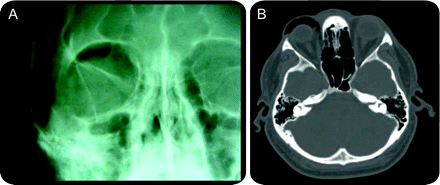

轨道肺气肿后鼻子吹